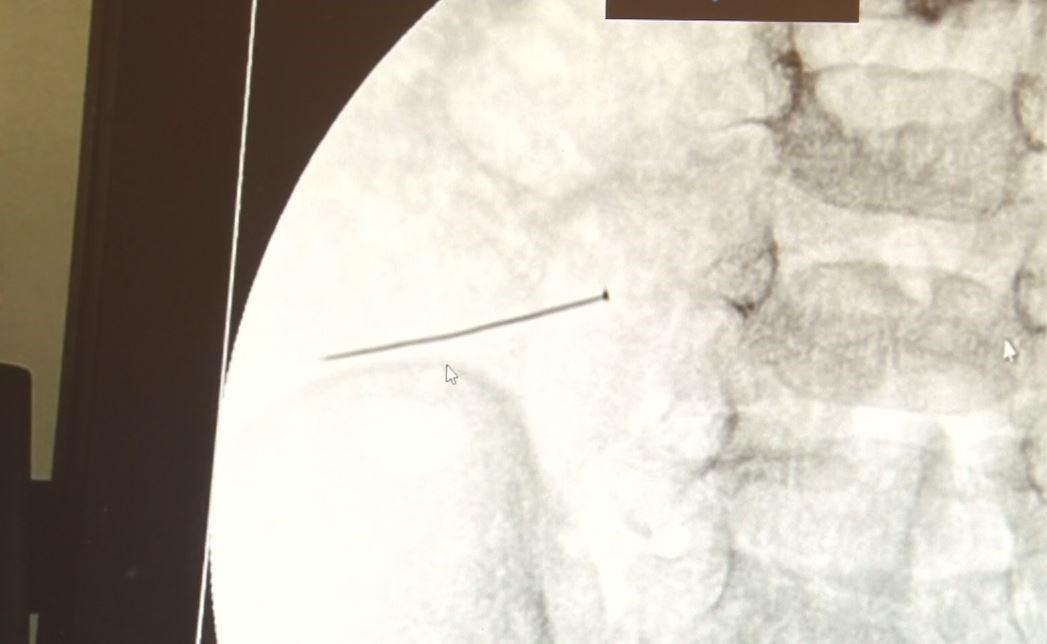

İstanbul'da 2 yaşındaki bir çocuk ciddi karın ağrısı ve kusma şikayetiyle hastaneye götürüldü. Yapılan tetkikler sonucu çocuğun, 3 santimlik iğne yuttuğu ve iğne yuttuğu bağırsağı delerek karın içerisine dolduğunu tespit edildi.

Burada yapılan tetkiklerde 2 yaşındaki çocuğun ince bağırsağında yaklaşık 3 santimlik toplu iğne olduğu ve bağırsağı deldiği belirlendi.

Yutulan cismin vücuda zarar verdiği noktada müdahale yapıldığını söyleyen Sefa Sağ, "Bu çocuğumuzda da aynen böyle bir hadise meydana gelmişti. Sanırım 1 gün önce ailenin yuttuğunu tahmin ettiği bir yabancı cisim, toplu iğne. Ertesi gün bağırsakta delinmeyle sonuçlanmış ve çocukta da ciddi semptomlar meydana getirmişti. Bu şekilde hasta bize başvurdu. Tetkikler sonucunda yabancı cismi tespit ettik, semptomları ve bulgularına göre de çocuğu ameliyata aldık. Yaklaşık 3 santim boyunda bir toplu iğnenin ince bağırsağı deldiğini, ince bağırsaktaki içeriğin de karın içerisine dolduğunu gördük. Ameliyatı başarılı bir şekilde tamamladık, yaklaşık 1 saat süren bir ameliyattı." dedi.